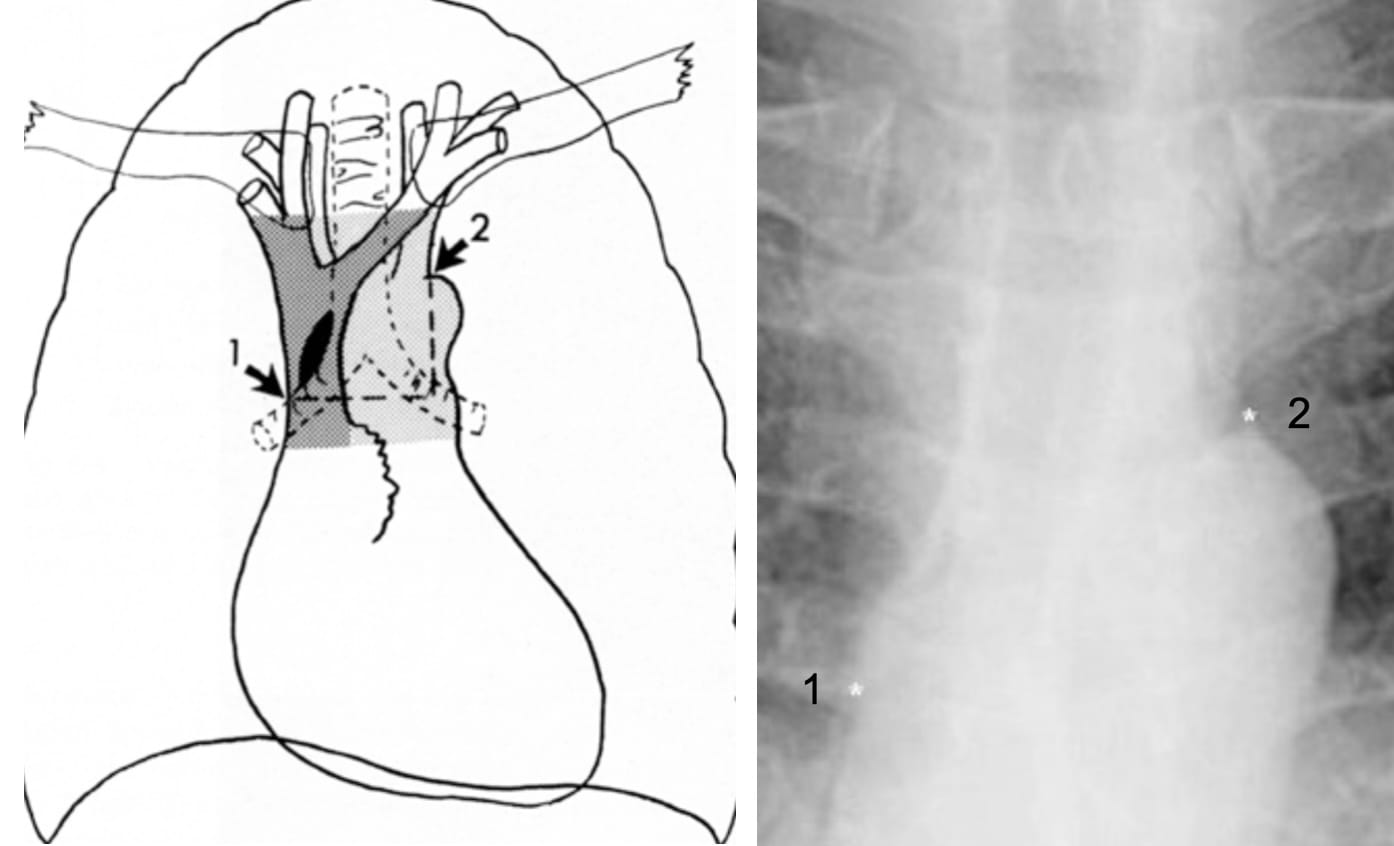

Diagnosis: Calcified fibrosing mediastinitis

The mediastinal tissue (blue box) encases the right superior pulmonary vein with resultant right upper lobe interstitial edema.